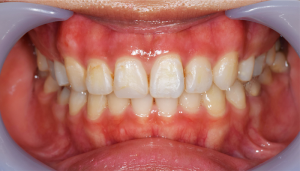

歯石除去

治療前

治療後

| 年齢 | 36歳・男性 |

| 主訴 | 歯石をとりたい |

| 治療内容 | 歯石除去 |

| 治療期間 | 30分 |

| 費用 | 約2,000円 |

| リスク・副作用 | ・歯ぐきの炎症が強いと歯石を取る際に出血することがあります。 ・処置後に歯がしみることがあります。 ・歯と歯の間に隙間ができるので、息が漏れ発音しにくいと感じることがあります。 ・歯ぐきの炎症が軽減すると歯ぐきが引き締まり、歯が長く見えることがあります。 |